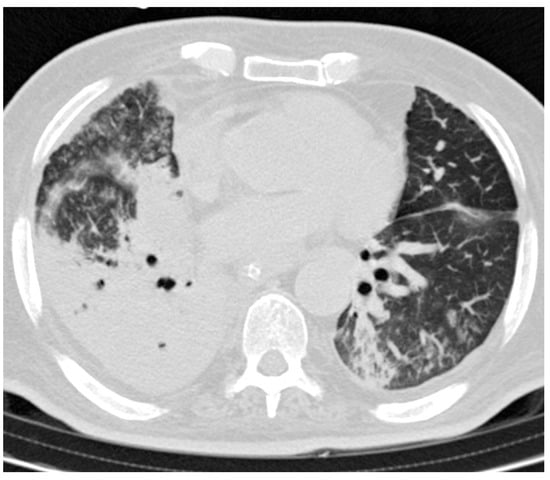

Alert Germ Infections: Chest X-ray and CT Findings in Hospitalized Patients Affected by Multidrug-Resistant Acinetobacter baumannii Pneumonia

3.3. CT Findings and Disease Distribution

3.4. Statistical Tests